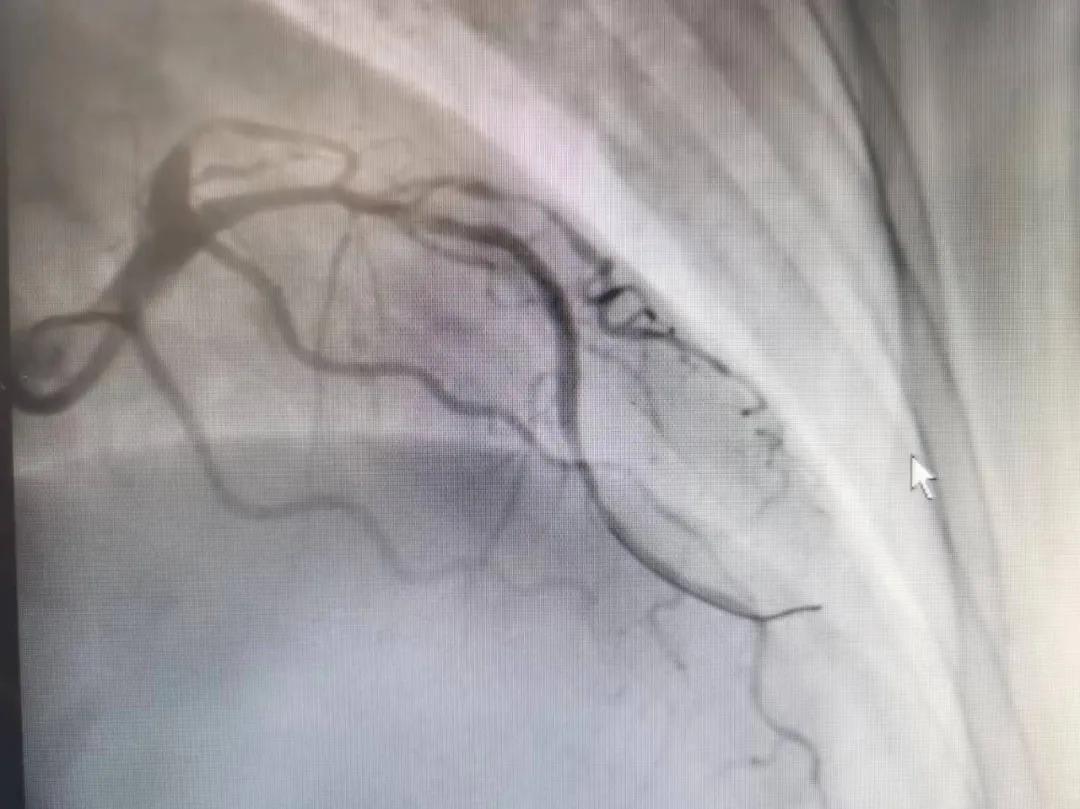

術(shù)后

王瑾院長和李慧新主任帶領(lǐng)介入團隊充分評估,決定行前降支冠狀動脈鈣化病變旋磨術(shù),術(shù)中應(yīng)用1.5mm旋磨頭,以15萬-17萬轉(zhuǎn)/分速度共對病變旋磨3次,累計旋磨時間60秒,后復(fù)查造影示鈣化明顯減輕,為后續(xù)操作創(chuàng)造了良好條件,隨后應(yīng)用預(yù)擴張球囊、切割球囊再次處理病變,并順利植入支架1枚,復(fù)查造影顯示支架膨脹及貼壁良好,無夾層、血腫、慢血流等情況,手術(shù)順利完成。患者術(shù)后無不適,胸悶、胸痛癥狀明顯緩解,順利出院。